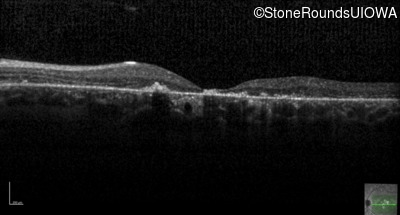

Age at visit: 26 years

OD OS